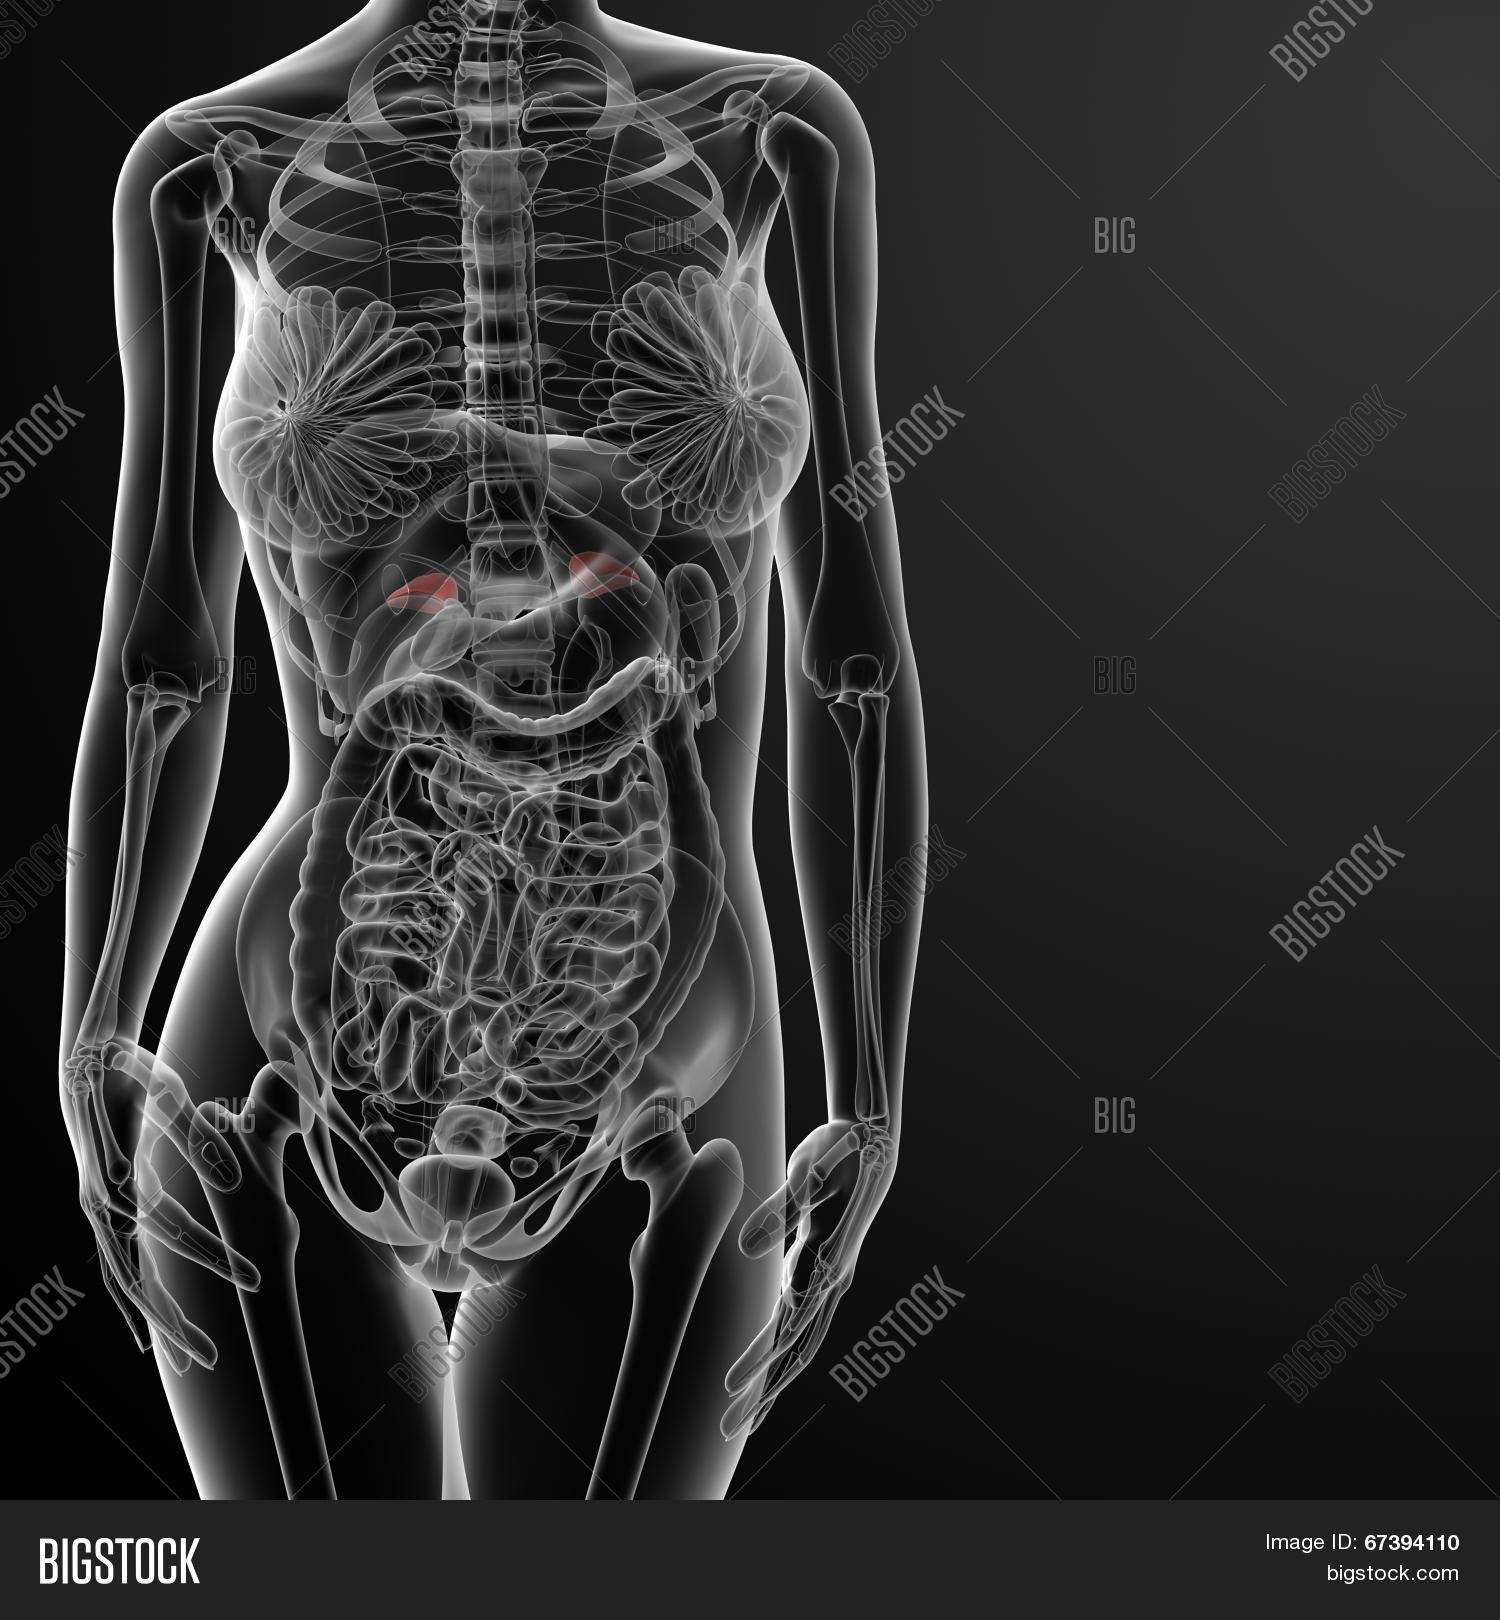

Рентгеновский эффект создает фантастические композиции в этих фотографиях девушки, чье тело становится прозрачным, демонстрируя скелет и внутренние органы. Она позирует в разных позах, ее силуэт светится загадочным свечением. Каждый кадр передает атмосферу научной фантастики и медицинского искусства. Ее кожа кажется полупрозрачной, позволяя увидеть кости и мышцы. Фотографии рассказывают о хрупкости человеческого тела и его внутренней красоте. Девушка то стоит в задумчивости, то делает грациозное движение. Эти иллюстрации вдохновляют на размышления о человеческой анатомии и уязвимости. Каждая картинка - это момент прозрения, когда внешнее уступает место внутреннему. Девушка воплощает образ современной Медузы, сочетающей красоту и загадочность.

Сквозь материю: тайны анатомии